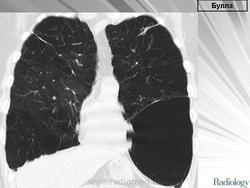

Булла.

Приложения:

slayd6789.jpgslayd7789.jpg